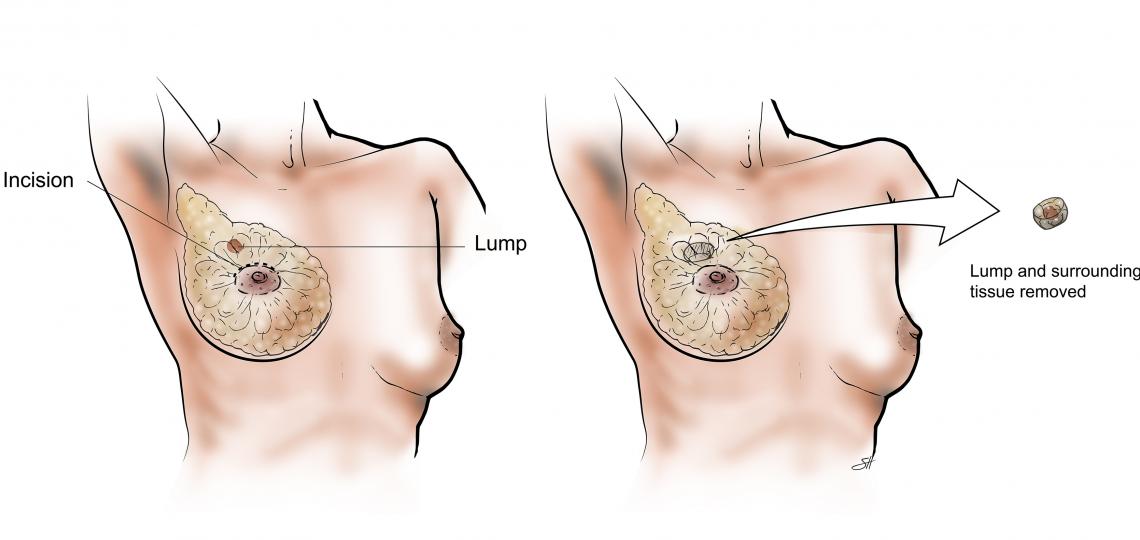

Lymph Node Biopsy Cervical or Axillary or Inguinal Under Ga

$1530Overview

Package includes:

Days in hospital : 3 to 4 Days (For patient and one attendant)

Days in hotel : 5 Days (For patient and one attendant)

Room type in hospital : Shared

Room type in hotel : Private

Hotel category: Standard

Value added benefits of the Lymph Node Biopsy Cervical or Axillary or Inguinal Under GA:

Ø Doctor consultation charges

Ø Lab tests and diagnostic charges

Ø Room charges inside hospital during the procedure

Ø Surgeon Fee

Ø Nursing charges

Ø Hospital surgery suite charges

Ø Anesthesia charges

Ø Routine medicines and routine consumables (bandages, dressings etc.)

Ø Food and Beverages inside hospital stay for patient and one attendant.

Extra benefits:

ü Interpreter

ü Visa assistance

Ø Site tourism of the city

Ø Follow up with the doctor

Ø Airport pick up and drop

Ø Free online consultation with the doctor

Ø Priority appointments with the doctor

Ø Room upgrade from sharing to private